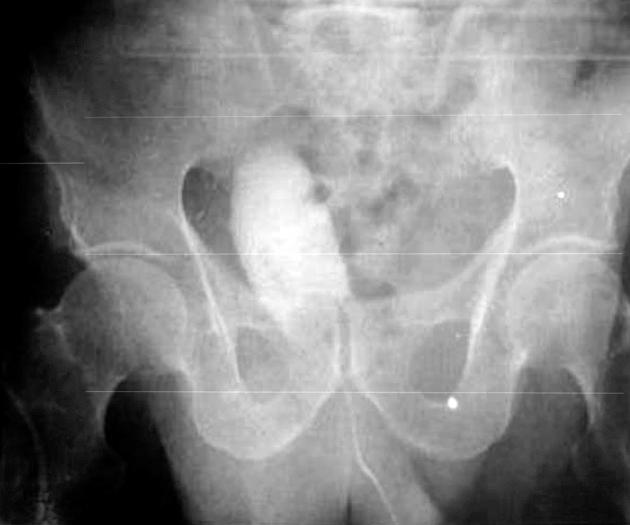

Gastric pouch after simple or radical cystectomy for benign and malignant bladder disease.

In this retrospective case series, we described our experience on seven gastric pouches (2 gastrocystoplasty and 5 gastric neobladders).

Postoperative complications were rare. Continence was defined as bladder capacity over 400 mL. Their follow-up period ranged from five months up to writing the article. One of the studied cases is still alive and awaiting renal transplantation.

Gastric pouch is a suitable segment for bladder cystoplasty and neobladder. Continence is mostly related to the capacity of pouch.